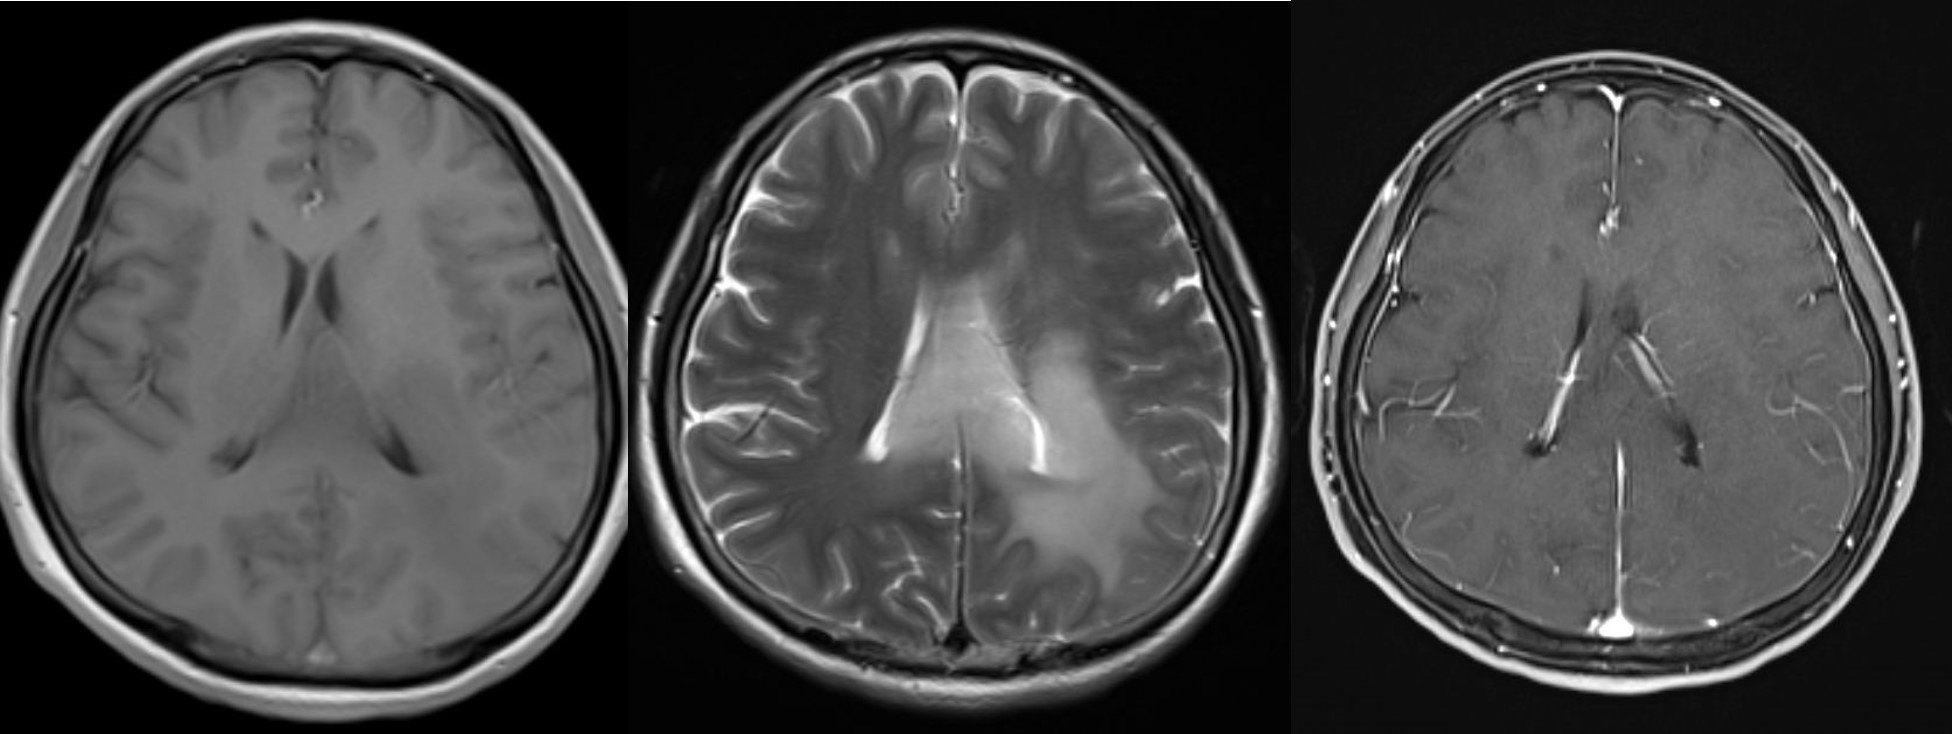

该患者为中年男性,因头痛头晕2个月就诊,头颅MRI示:左侧丘脑、左侧枕叶近胼胝体压部、四脑室周边异常信号改变,TI呈低信号,T2呈高信号,无明显强化。

患者局麻性行神经导航下脑立体定向活检术,穿刺八点为左侧枕叶深部病变,术后病理提示:胶质增生。